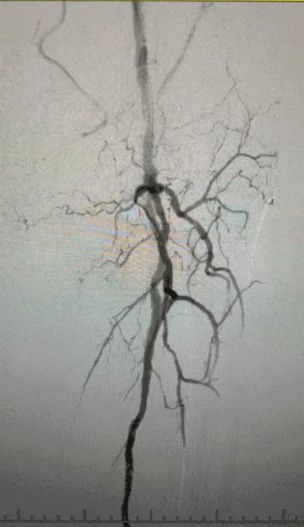

·Physical Examination: Weak femoral pulses; absent popliteal and dorsalis pedis pulses; ulceration on left first toe; necrosis on right first and second toes

·Preoperative Imaging: Severe, diffuse calcified stenosis in bilateral lower limb arteries